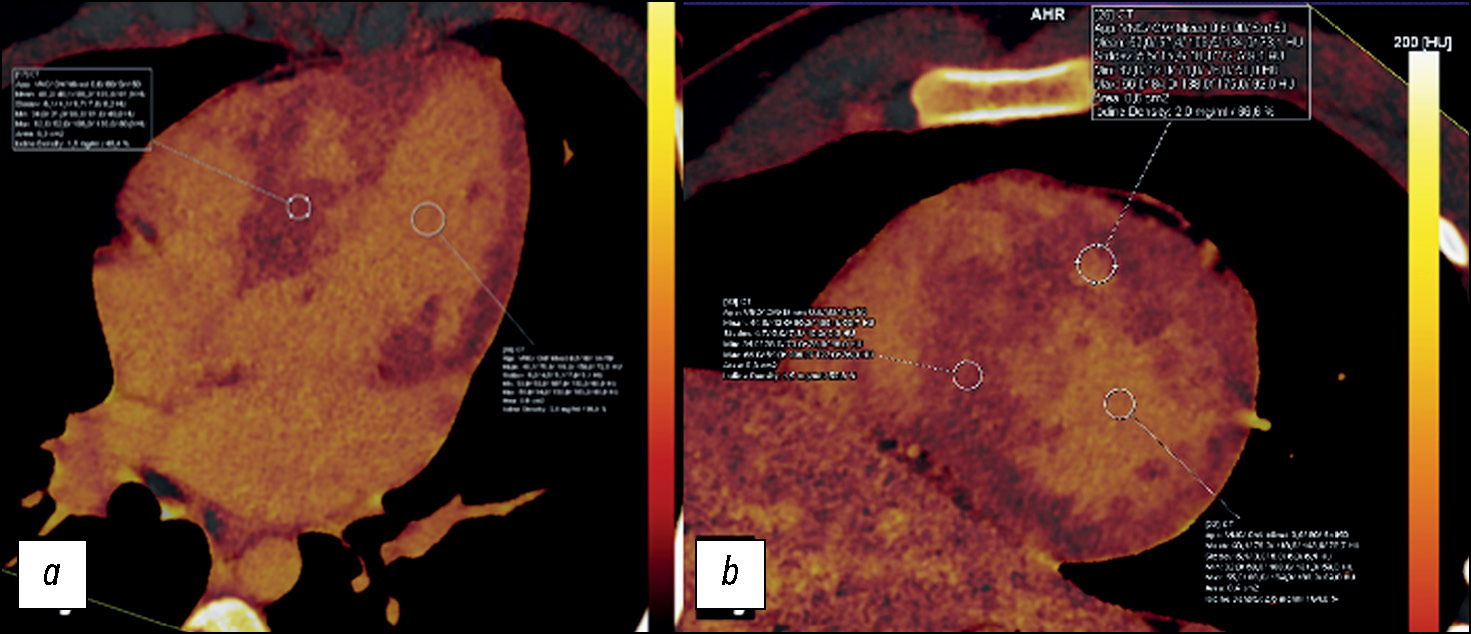

Оценка структурных изменений миокарда методом ДЭКТ выполнена 13 (27%) пациентам. У всех пациентов выявлены очаговые накопления йода на картах отсроченного контрастирования (рис. 8).

Рис. 8. Пример визуальной оценки очагового накопления йода в сегментах миокарда ого желудочка по данным йодной карты двухэнергетической компьютерной томографии: a — короткая ось сердца; b — аксиальная проекция сердца.

Зоны интрамиокардиального очагового накопления йода в 10 из 13 (76%) случаев локализировались по МЖП. Кроме того, на йодных картах отсроченного контрастирования проведен подсчёт фракции внеклеточного объёма (ECV) на среднем уровне ЛЖ. Значение ECV по данным йодных карт определялось следующим выражением:

В нашей работе у 10 из 13 (76%) пациентов отмечалось увеличение значения показателя в одном и более сегментах (N=25,4%). Среднее значение ECV миокарда ЛЖ по данным ДЭКТ составило 30,58% (95% доверительный интервал 27–34%) и превышало нормальные диапазоны.